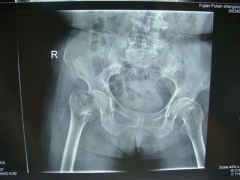

7月9日,莆田盛興醫(yī)院為一名89歲的女性髖部骨折患者順利實(shí)施了手術(shù)。   數(shù)日前,東……

近日,平海鎮(zhèn)90歲高齡的周阿婆即將出院。她感慨地對(duì)筆者說(shuō):“真沒(méi)想到我還能下床走路……